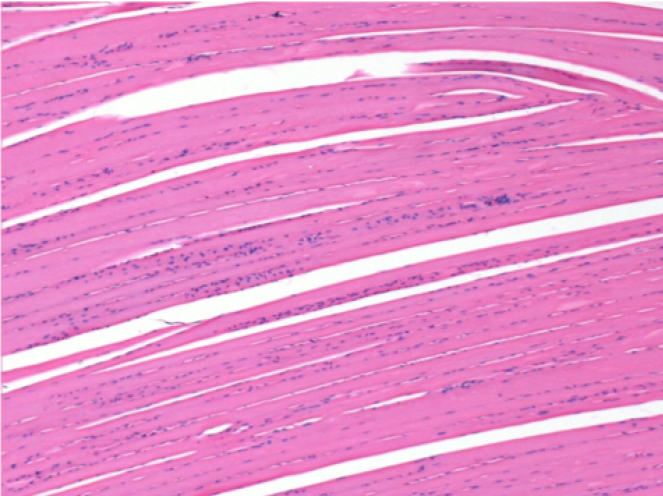

7 months after Endopeel Injection

7 months (D210)after Endopeel IM Injection 0.1ml in the right pretibial muscle.

Complete Restitutio ad integrum after 7 months

L : Control-100xD210

R:100xD210

L :Control 50xD210

R50X-D210